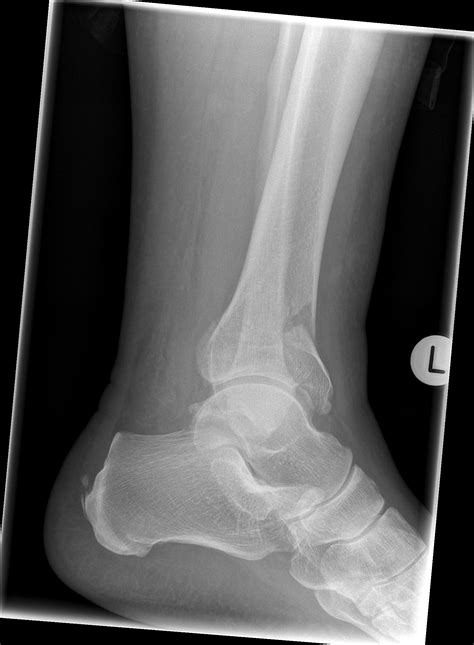

• X-rays: Standard radiographs to visualize the fracture pattern and the extent of displacement.

Understanding the intricacies of a *Pilon Bone Fracture* is crucial for anyone involved in orthopedic care or anyone who has experienced this type of injury. A *Pilon Bone Fracture* occurs at the distal end of the tibia, the larger of the two bones in the lower leg, and often involves the articular surface of the ankle joint. This type of fracture can be particularly challenging to treat due to its complex nature and the potential for long-term complications.